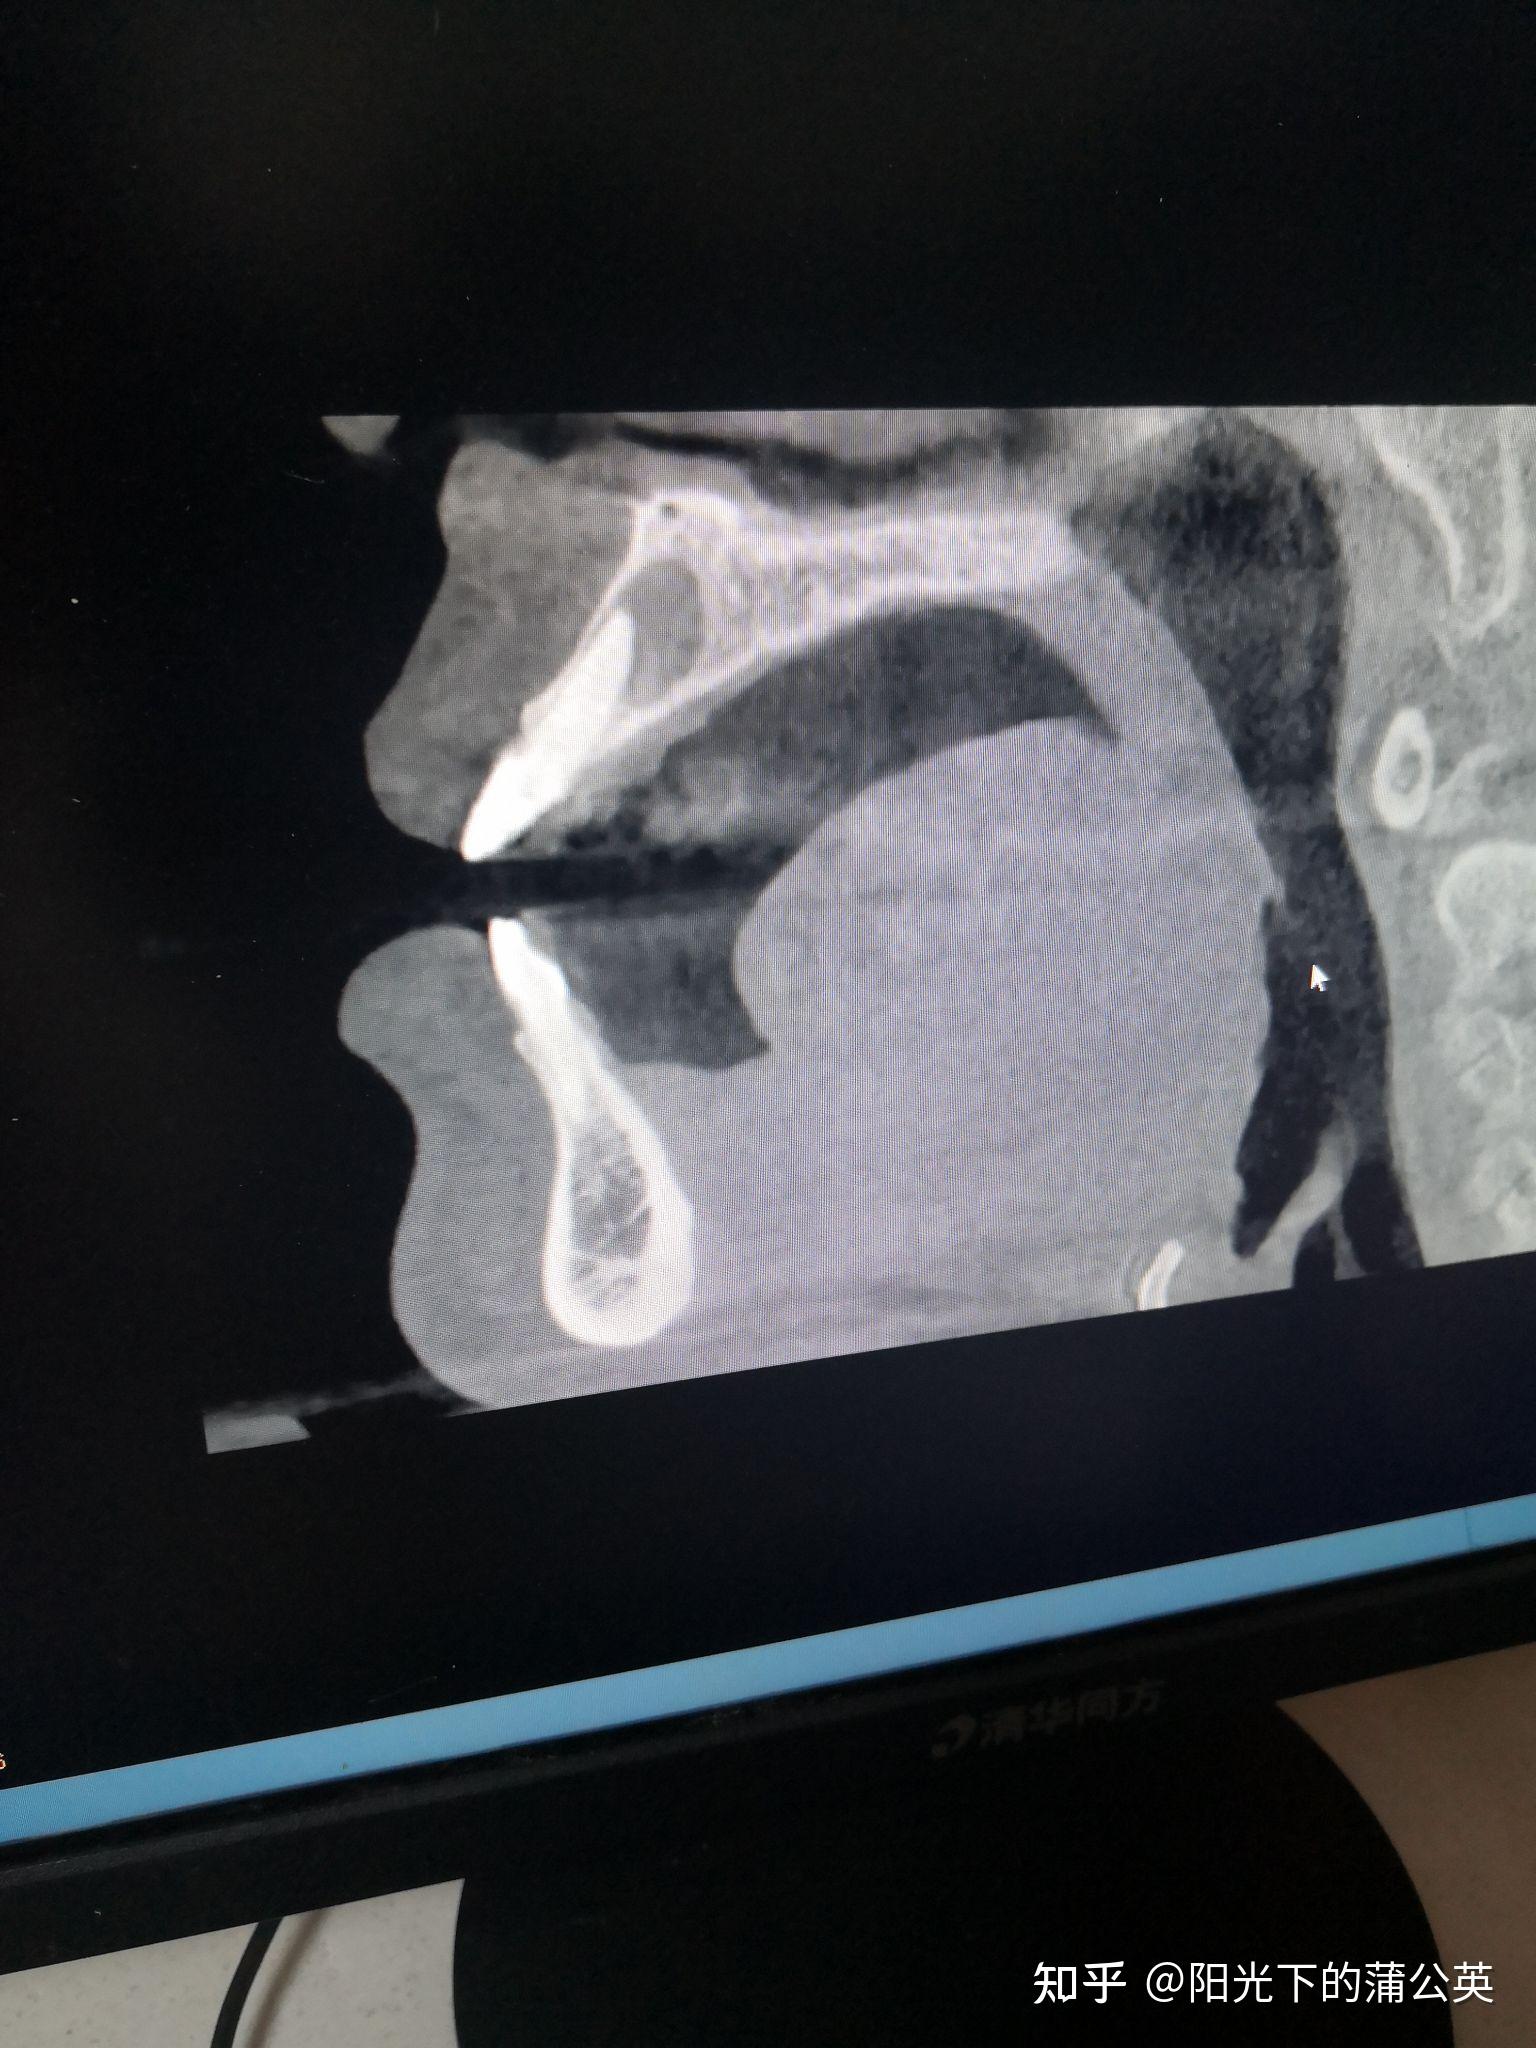

上颌前牙根尖囊肿摘除即刻种植一例

记录自己根尖手术